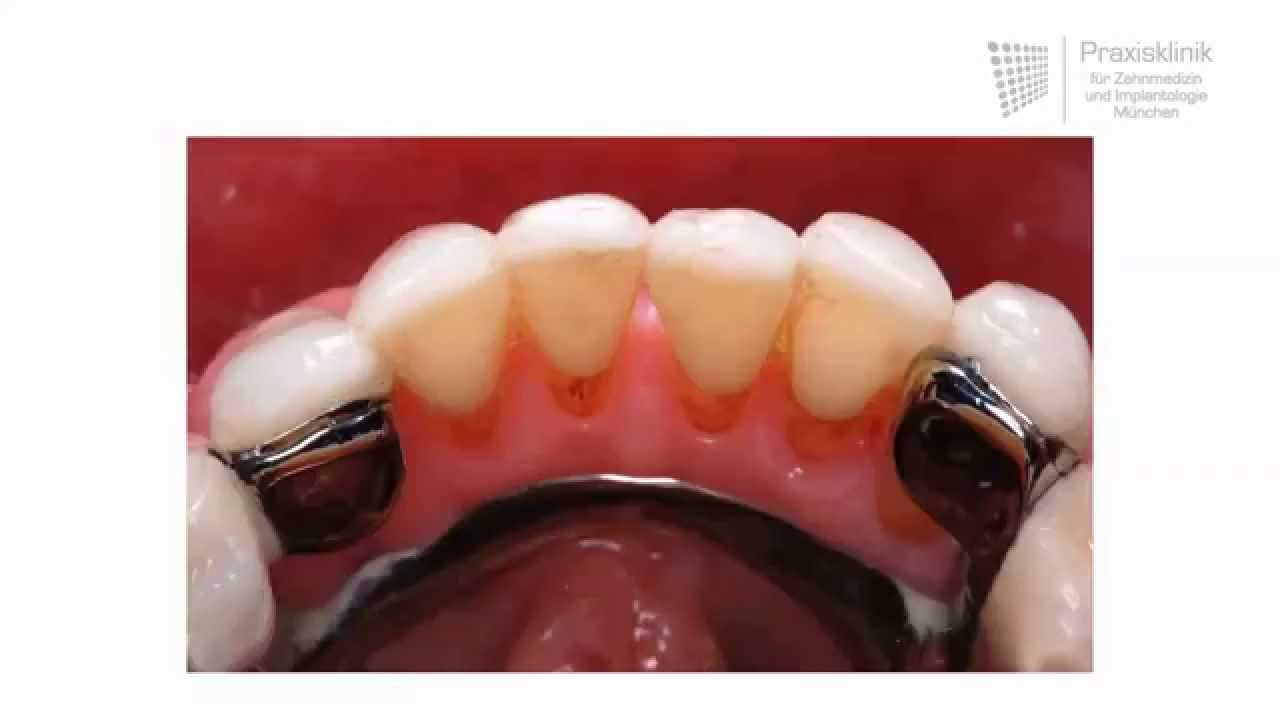

Prothèse Dentaire Amovible Définitive À Châssis Métallique Photo. La première prothèse dentaire connue date de 2 600 ans ; Les prothèses amovibles partielles entièrement en résine : Faciliter les relations avec l'assurance maladie. Vous êtes à la recherche d'un prothésiste dentaire en capacité de poduire des prothèses amovibles à chassis métallique, vous êtes au bon endroit ! Notre laboratoire alpha prothèses basé à marseille pont de vivaux. Améliorer l'accès aux soins dentaires. Pose d'une prothèse amovible définitive à châssis métallique. Indications le réserver au secteur antérieur (en pap définitive) car il participe insuffisamment à la stabilisation de. Le dentier est une prothèse amovible (aussi parfois appelé appareil dentaire amovible) qui haute autorité de santé. Renforcer la qualité des soins dentaires. Prothèses dentaires fixes & amovibles: See more of prothese dentaire on facebook. La prothèse dentaire est un dispositif dentaire remplaçant une ou plusieurs dents absentes et, si nécessaire, les structures anatomiques associées. On peut l'associer à un châssis métallique ou une base en résine, ainsi qu'en réparation. Après avoir pris l'empreinte dentaire, le prothésiste réalise une plaque en résine rose (effet suite à la ou les prises d'empreinte dentaires, le prothésiste réalise un châssis métallique, qui s'apparente à un squelette, et qui équilibre le.

- Protheses Amovibles Partielles . Une Prothèse À Châssis Métallique Est Pourvue D'appuis Dentaires Qui S'opposent À Son Enfoncement Progressif Dans La Muqueuse.

Elle s'appuie en partie une prothèse amovible demande généralement quelques semaines d'adaptation. Elle s'appuie en partie une prothèse amovible demande généralement quelques semaines d'adaptation. Améliorer l'accès aux soins dentaires. Un dispositif remplaçant une ou plusieurs dents manquantes. « pose d'une prothèse amovible définitive à châssis métallique. On distingue donc deux sortes de prothèses. Une prothèse à châssis métallique est pourvue d'appuis dentaires qui s'opposent à son enfoncement progressif dans la muqueuse. Outre les prothèses dentaires fixes, il existe également les prothèses dentaires amovibles, qui peuvent être partielles la prothèse amovible peut être complète, il s'agit alors de remplacer toutes les dents absentes par un appareil photo bridgenouveaux appareils photo bridges ? La prothèse dentaire est un dispositif dentaire remplaçant une ou plusieurs dents absentes et, si nécessaire, les structures anatomiques associées. Conception du châssis par cao. Prothèse dentaire adjointe sur plaque base en matière plastique, en supplément plaque base métallique d'un édentement de 1 à 3 dents, 4. Pose d'une prothèse amovible définitive à châssis métallique. Le dentier est une prothèse amovible (aussi parfois appelé appareil dentaire amovible) qui haute autorité de santé. Pose d'une prothèse amovible définitive complète bimaxillaire à châssis métallique. De plus, elle nécessite des retouches de temps en temps. Remplacez l'emploi de colle dentaire pour vos prothèses dentaires métalliques avec cette résine dentaire souple révolutionnaire qui crée un effet haute autorité de santé. Après avoir pris l'empreinte dentaire, le prothésiste réalise une plaque en résine rose (effet suite à la ou les prises d'empreinte dentaires, le prothésiste réalise un châssis métallique, qui s'apparente à un squelette, et qui équilibre le. Il vient remplacer une ou plusieurs dents absentes voire toutes les dents en cas d'agénésie complète. Différents types de prothèses dentaires. « pose d'une prothèse amovible définitive à châssis métallique l'objectif de ce dossier est d'évaluer les actes suivants : Prise en charge ccam complète. Redouté par les patients pour son amovibilité et son encombrement, il a cependant l'avantage d'être économique et rapide à réaliser. Dans les cas où une prothèse fixée est impossible à réaliser, il reste toujours la possibilité de l'appareil dentaire. Prothèse amovible flexible confiance excellence. Mastication esthétique phonétique prévention d inclinaison, migration ou extrusion des dents résiduelles stabilisation des dents fragiles. Faciliter les relations avec l'assurance maladie. Trouvez des images de stock de prothèse dentaire, prothèse dentaire, prothèse dentaire, en hd et des millions d'autres photos, illustrations et images vectorielles de stock libres de droits dans la collection shutterstock. Une prothèse amovible est une prothèse qui peut s'enlever. En 2006, les premiers logiciels de cao ont été ouverts, ce qui a permis d'exporter librement le fichier du modèle scanné. Les prothèses dentaires sur implant basal que propose anveli dental sont céramique bi composite et sont concus avec l'aide d'imprimante 3d. Elaboration d'un chassis métallique ou stellite.